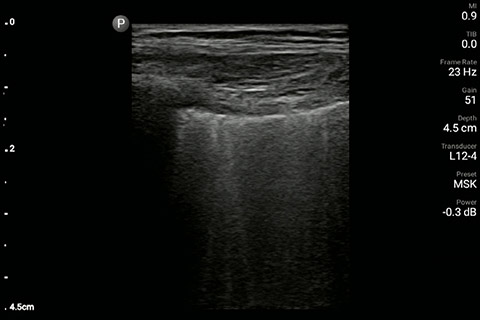

The patient had reduced LV systolic function without new or severe valvular pathology, a dilated, non-collapsing IVC, and diffuse B lines (left greater than right) on lung ultrasound imaging.

Lung image of the left chest

M-mode demonstrating lung sliding